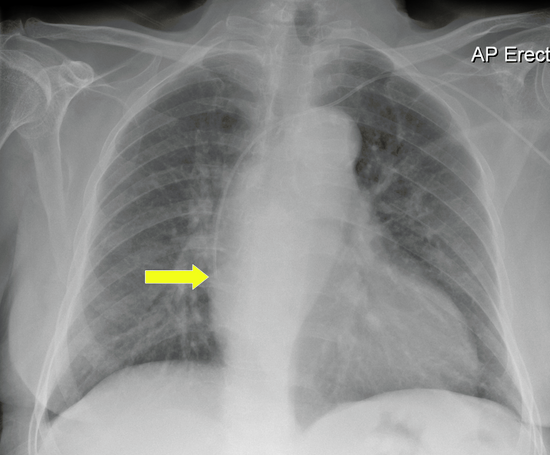

Chest x-ray:

Figure 3: Chest x-ray with catheter tip at cavoatrial junction